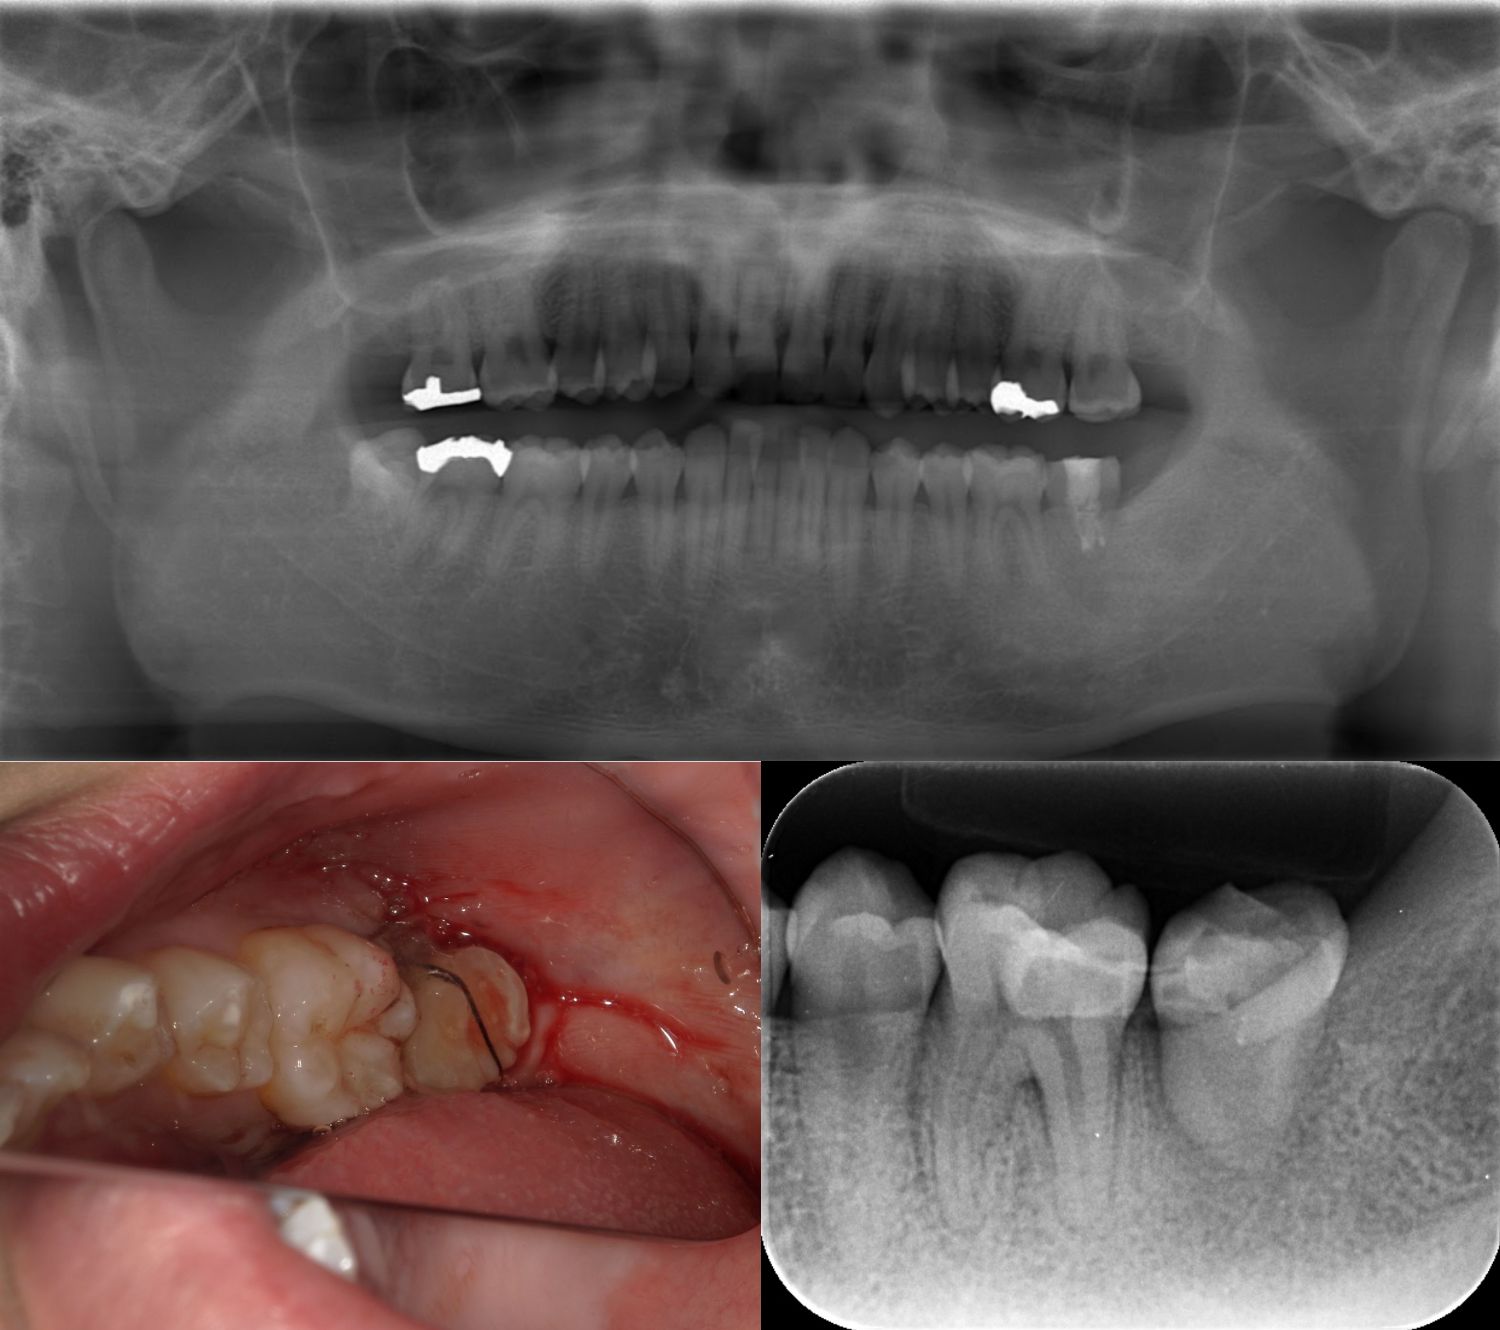

エクストリュージョン(牽引) 2019.07.17虫歯治療の症例 他の病院にて抜歯を宣告され来院され、なんとか残す方法を伝え挑戦した結果歯を残すことができました。治療期間:1年半費用:6万円(被せ物代を除く)リスク:虫歯が想像以上に深い場合は抜歯になる可能性がある... 続きを読む

歯根の膿の袋を治療し、健康な歯の部分を引き出した治療 2019.07.17虫歯治療の症例 歯の根の膿の袋を治療し、健康な歯の部分を引き出して、被せ物を行った治療(エクストリュージョン・牽引)。治療期間:1年費用:6万円(被せ物を含まない)リスク:虫歯が深い場合に抜歯に至る可能性がある。歯... 続きを読む

抜歯せずに噛めるようになったエクストリュージョン(牽引)処置 2019.07.17虫歯治療の症例 上下とも深い虫歯になり抜歯を宣告されたが引き出すことで抜歯せずに噛めるようになったエクストリュージョン(牽引)処置です。治療期間:12ヶ月費用:1本6万円 2本目以降5万円(被せ物を除く)リスク:虫歯が深... 続きを読む